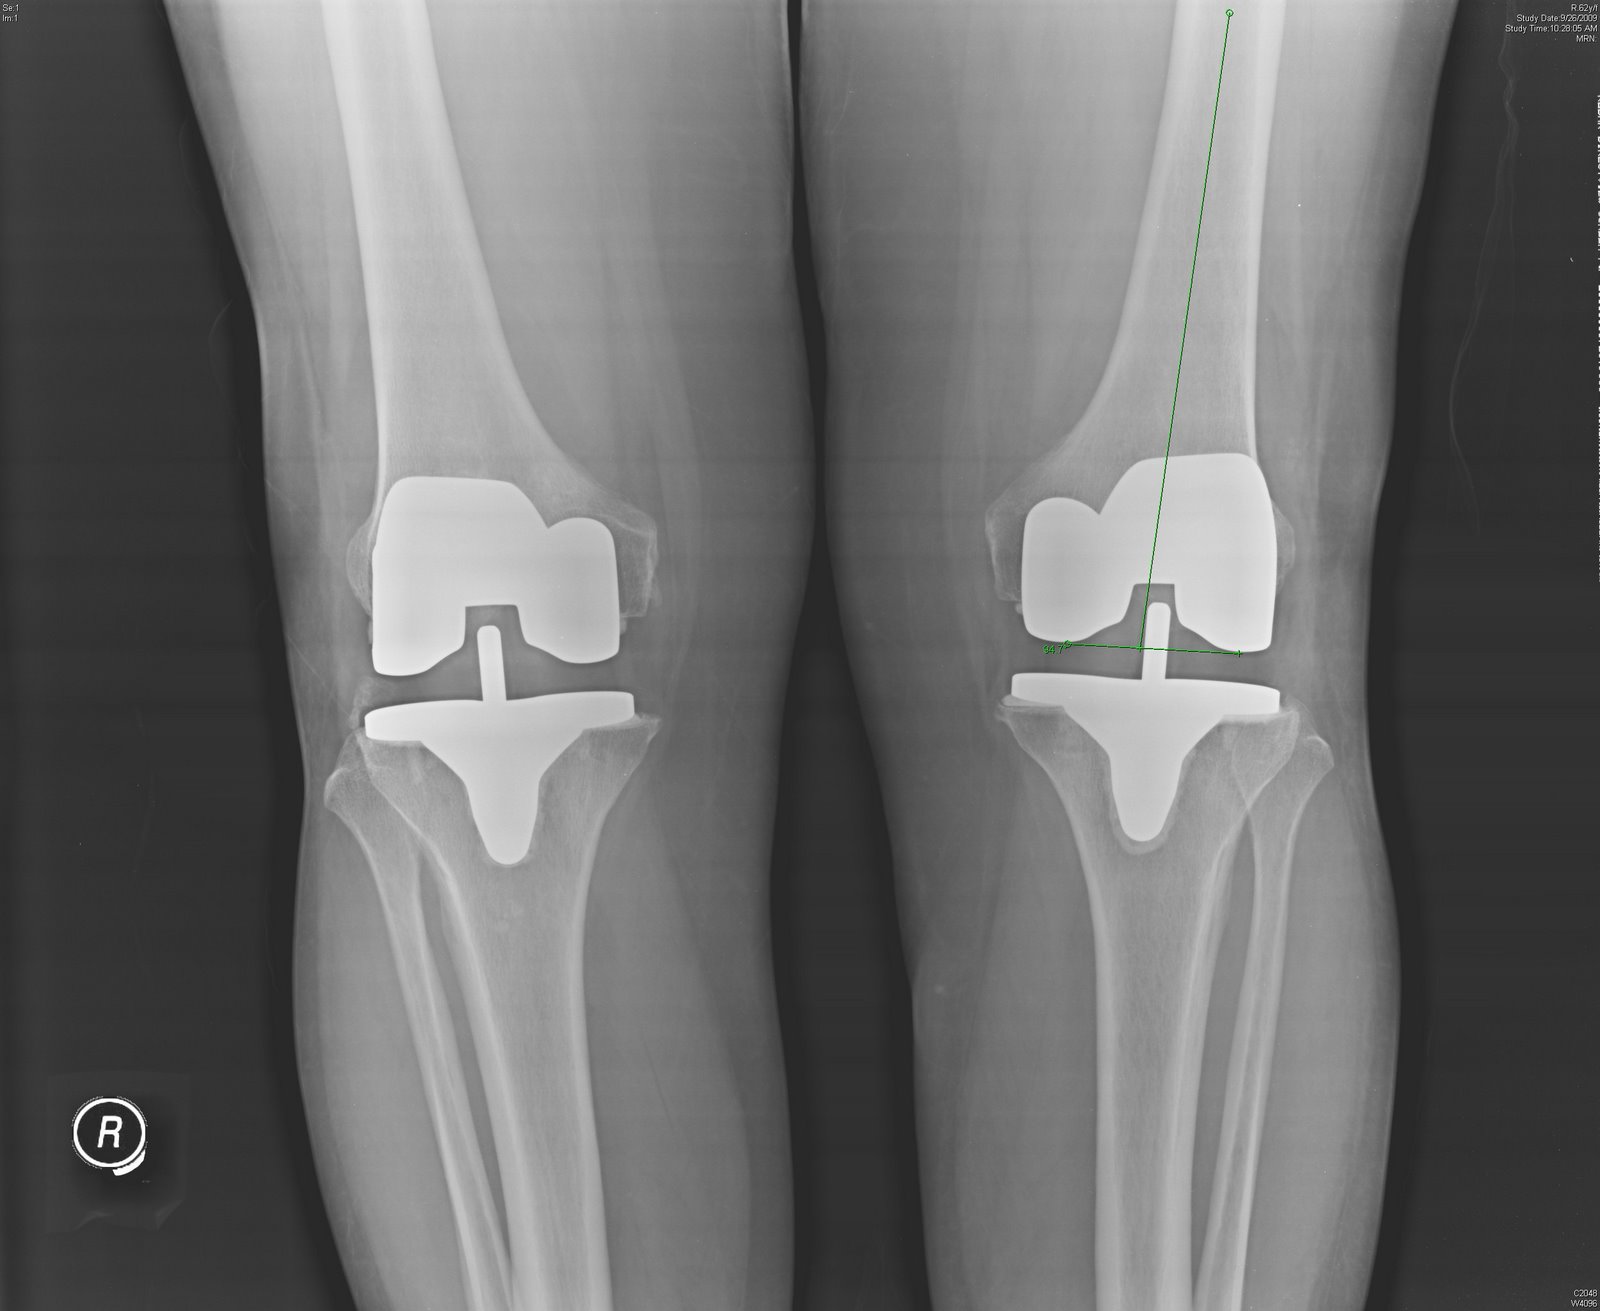

Bilateral Knee Replacement (Simultaneous) Complete Orthopedics How Much Does Bilateral Knee Replacement Cost Either surgery may involve any combination of total knee replacement or partial. People who have a double knee replacement only have to. Less time off from work. Learn the upsides and downsides of double knee. A knee replacement is carried out to treat knee pain, usually due to knee osteoarthritis, which is gradual wear and tear of the joint. The. How Much Does Bilateral Knee Replacement Cost.

Bilateral total knee replacement (TKR) in an obese lady Bone & Joint How Much Does Bilateral Knee Replacement Cost Less time off from work. People who have a double knee replacement only have to. Both knees are replaced at the same time. A knee replacement is carried out to treat knee pain, usually due to knee osteoarthritis, which is gradual wear and tear of the joint. 100k+ visitors in the past month What’s the cost of a knee replacement. How Much Does Bilateral Knee Replacement Cost.